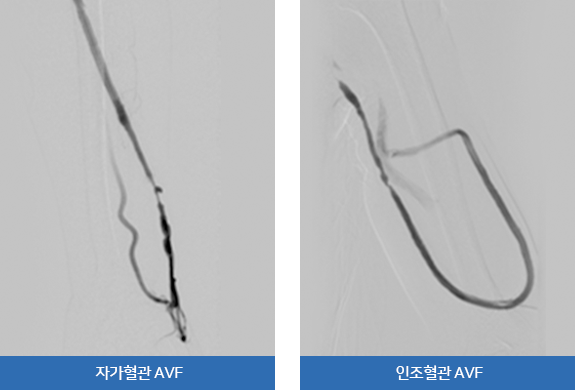

혈액투석샛길(AVF)는 동맥과 정맥을 직접 연결하여 만드는 자가혈관 AVF와 인공혈관을 동맥과 정맥사이에 삽입하는 인공혈관 AVF

두 가지 방법이 있습니다. 혈액투석샛길은 영구적으로 사용할 수 없으며 점차적으로 협착, 폐쇄, 혈전, 동맥류 등의 합병증을 동반한

기능부전이 생기는데 이 때 인터벤션을 통한 혈액투석샛길 재개통술이 필요합니다.